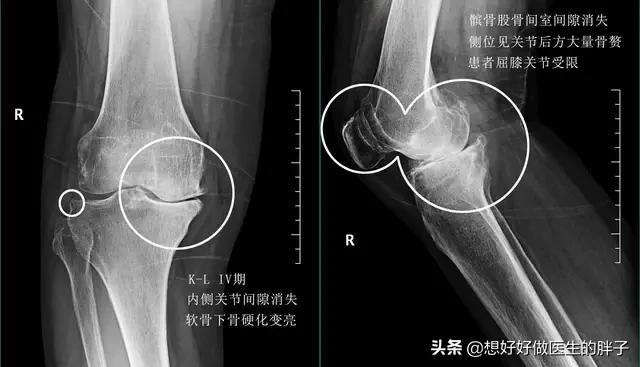

●当软骨磨损发展到中期,软骨可能已经发生了碎裂,甚至有部分软骨发生了脱落,那么此时在核磁上影像结果是比较清晰的,但是在x线上可能会没有异常,因为在x线上我们无法发现软骨的改变。所以在这个时候往往结合患者的症状查体以及核磁检查,可以做出明确的诊断。

●当软骨磨损特别严重,患者疼痛比较明显的时候,就没有必要浪费金钱进行核磁检查了,因为此时因为软骨磨损的特别严重,髌骨以及后方的股骨关节间隙已经出现了明显的狭窄,而且形态已经发生了明显的改变,做普通x线检查就可以明确问题了。

●当软骨磨损特别严重以后,关节间隙会有明显的狭窄,患者关节功能将会明显的受限,而且会伴有难以忍受的疼痛,此时可能需要进行髌骨股骨关节置换,才能彻底的帮助患者解决问题了。